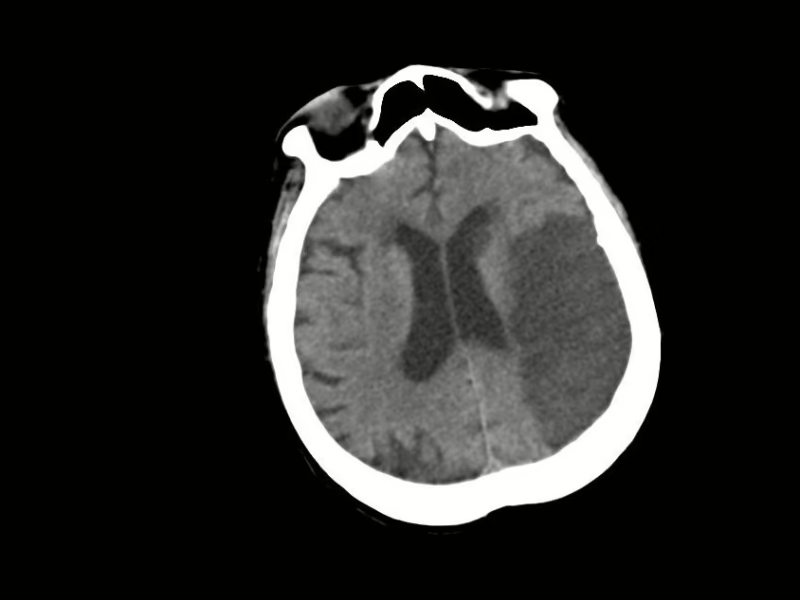

Sustancia gris y blanca, hacia lóbulo frontal, parietal y temporal izquierdos, con área hipodensa, irregular, bien definida, que mide 6.21 X9.27X 4.27 cm, en su eje longitudinal, anteroposterior y trasversal respectivamente, con leve efecto de masa hacia ventrículo lateral izquierdo. A nivel de lóbulo insular derecho, con pequeña área ovoidea, regular, bien definida, isodensa a líquido cefalorraquídeo, que mide 13.7 X 8.9 mm. Resto con adecuada diferenciación.

Surcos y cisuras, periférico área hipodensa de lóbulo frontal, parietal y temporal izquierdos con disminución de su amplitud y profundidad esto por edema citotóxicos. Resto con aumento de la amplitud y de profundidad.

Núcleos de la base, y núcleo caudado izquierdo, con área ovoidea, regular, bien definida, que mide 12.9 X 8.4 mm, con efecto de masa. Resto de morfología y densidad habitual, simétricos

Sistema ventricular, con aumento su amplitud. Índice de Evans de 0.32

EN EL PRESENTE ESTUDIO TOMOGRAFICO, EXISTEN EVENTO VASCULAR ISQUÉMICO AGUDO A NIVEL DE LÓBULO FRONTAL, PARIETAL Y TEMPORAL IZQUIERDO, ASÍ COMO TAMBIÉN EVENTO LACUNAR AGUDO A NIVEL DEL NÚCLEO CAUDADO IZQUIERDO, ESTOS CON EDEMA ASOCIADO.

EVENTO LACUNAR ISQUÉMICO CRÓNICO EN LÓBULO INSULAR DERECHO.